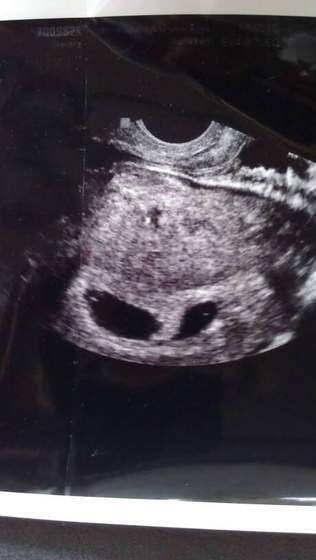

Ciąża bliźniacza

Między moimi różnica jest diametralna... Mieszkam w Niemczech. Nie mam zastrzeżeń do mojego lekarza ,jest naprawdę dobrym doc i człowiekiem :) postaram się wrzucić foto z fasolkami